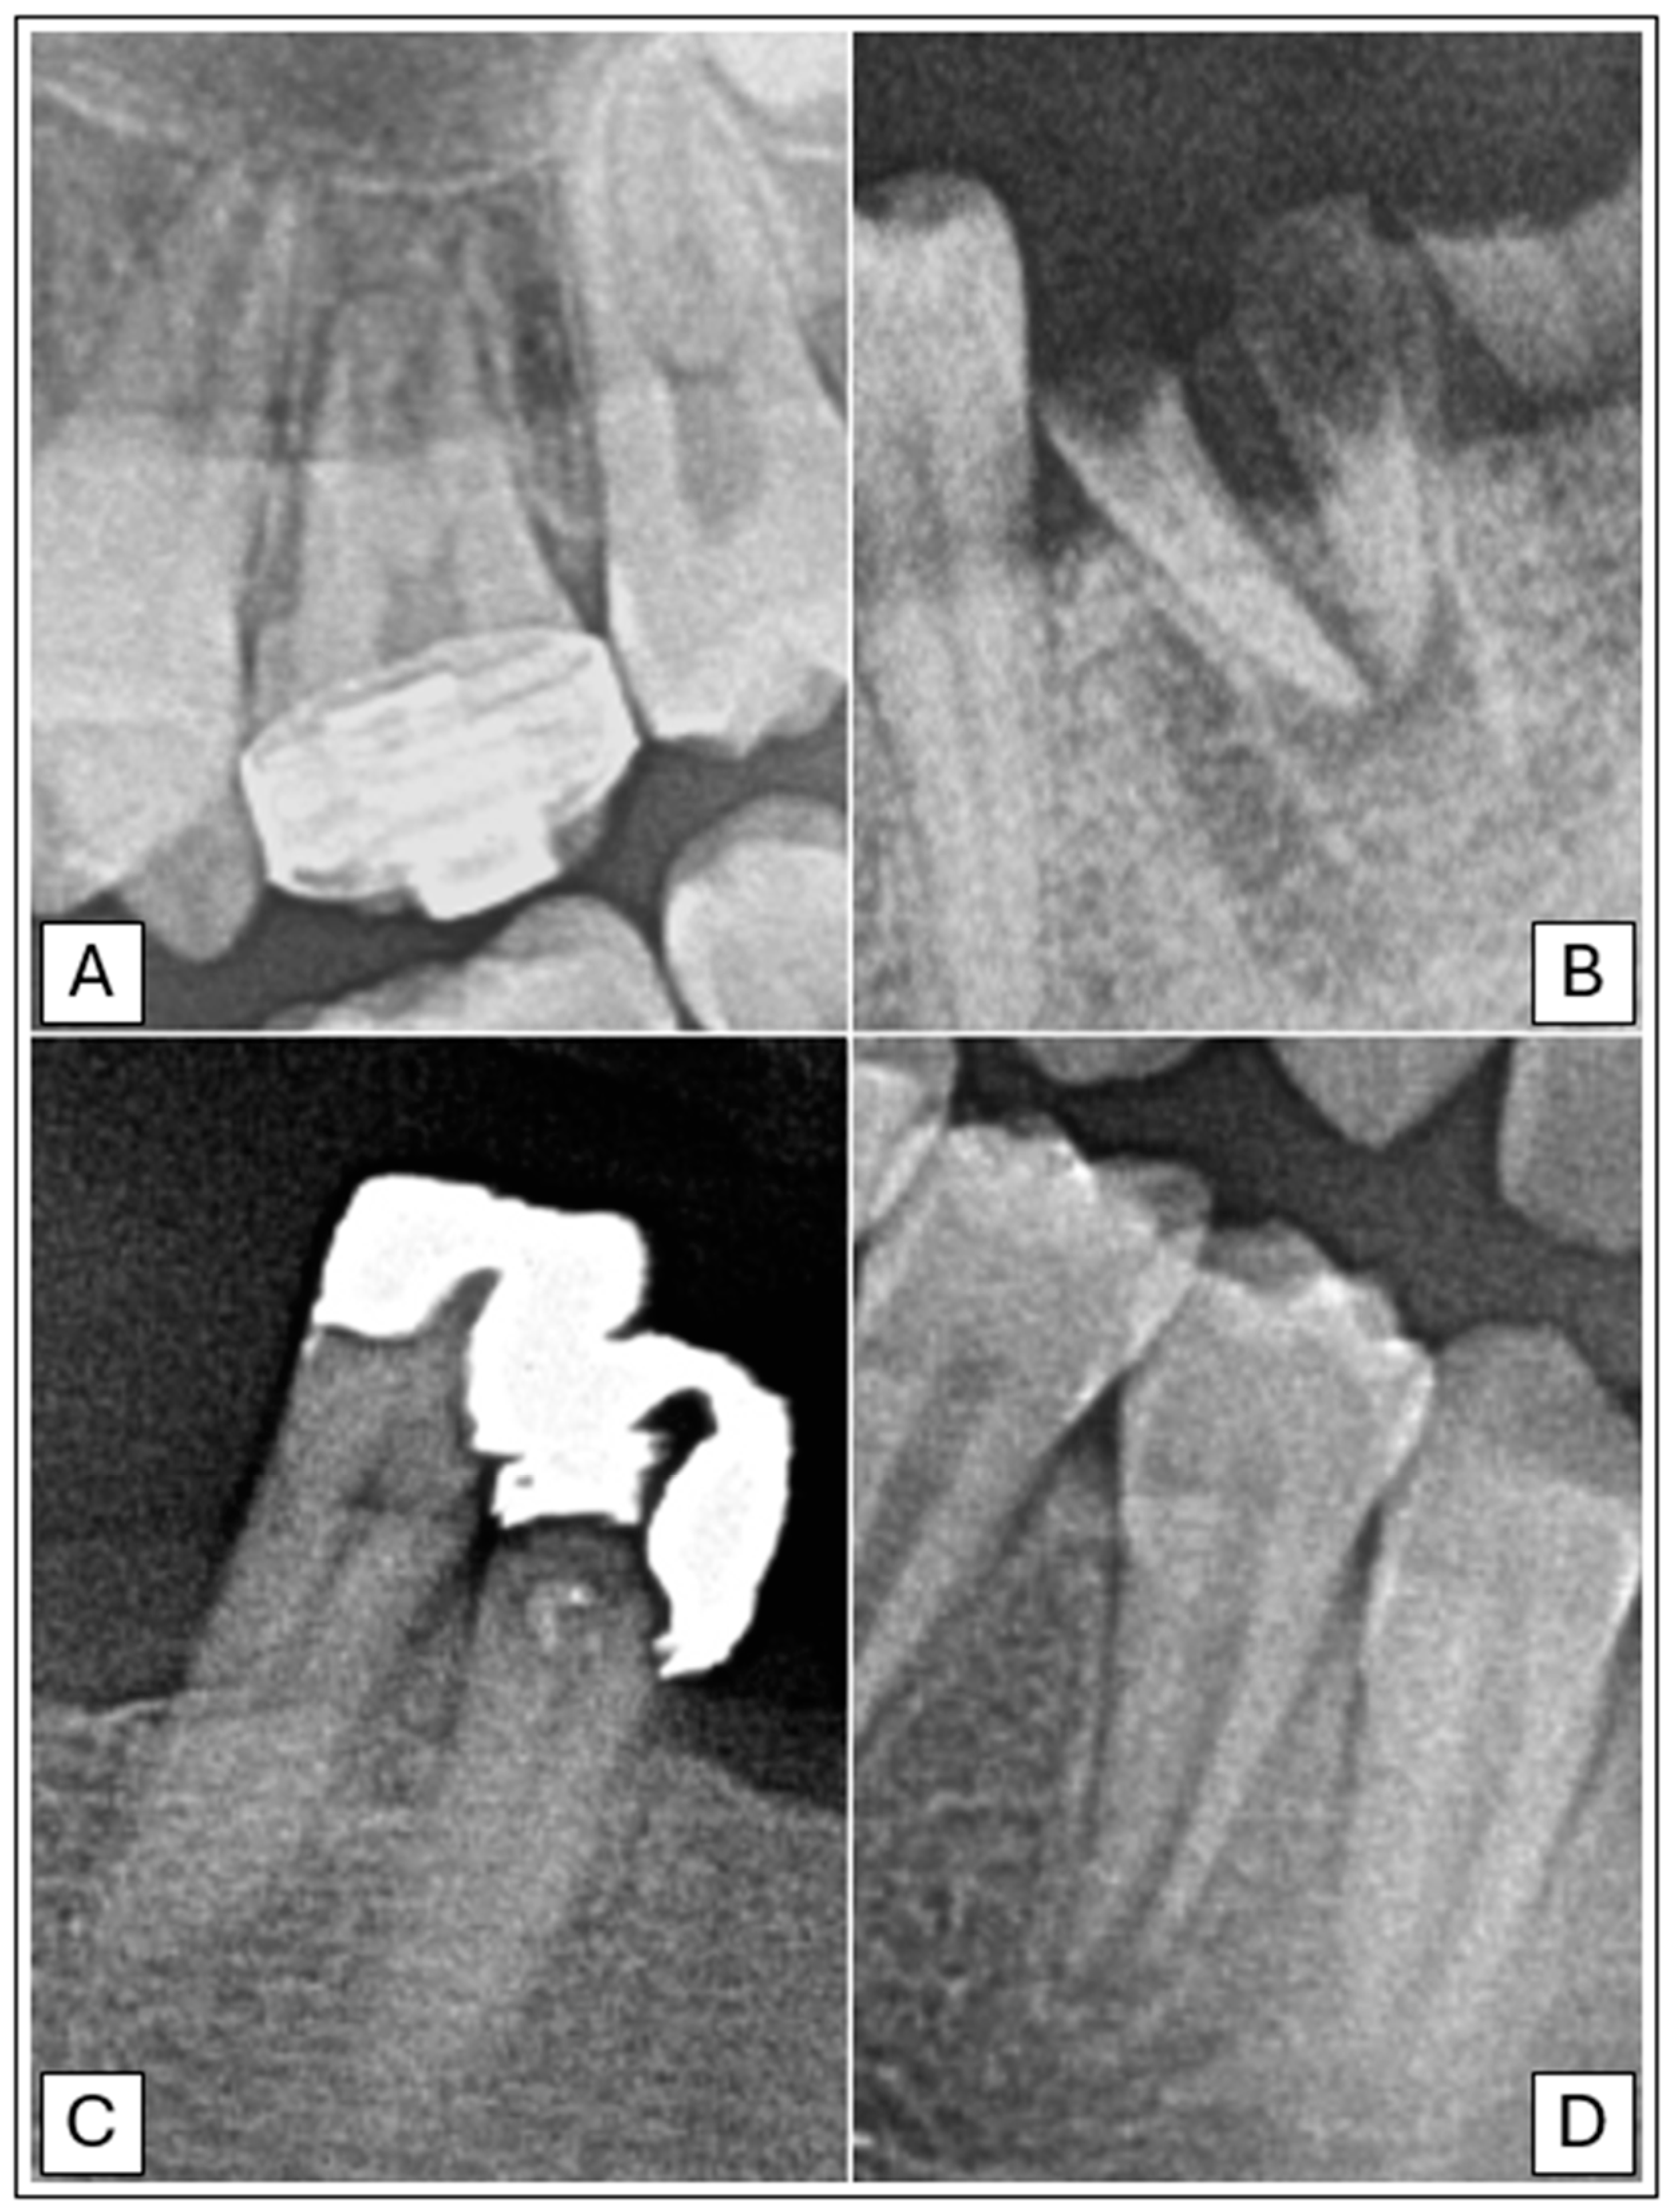

- Lofthag-Hansen, S.; Huumonen, S.; Gröndahl, K.; Gröndahl, H.-G. Limited cone-beam CT and intraoral radiography for the diagnosis of periapical pathology. Oral Surg. Oral Med. Oral Pathol. Oral Radiol. Endod. 2007, 103, 114–119. [Google Scholar] [CrossRef]

- Ramis-Alario, A.; Tarazona-Alvarez, B.; Cervera-Ballester, J.; Soto-Peñaloza, D.; Peñarrocha-Diago, M.; Peñarrocha-Oltra, D.; Peñarrocha-Diago, M. Comparison of diagnostic accuracy between periapical and panoramic radiographs and cone beam computed tomography in measuring the periapical area of teeth scheduled for periapical surgery. A cross-sectional study. J. Clin. Exp. Dent. 2019, 11, e732–e738. [Google Scholar] [CrossRef]

- Kazimierczak, W.; Wajer, R.; Wajer, A.; Kiian, V.; Kloska, A.; Kazimierczak, N.; Janiszewska-Olszowska, J.; Serafin, Z. Periapical Lesions in Panoramic Radiography and CBCT Imaging—Assessment of AI’s Diagnostic Accuracy. J. Clin. Med. 2024, 13, 2709. [Google Scholar] [CrossRef]